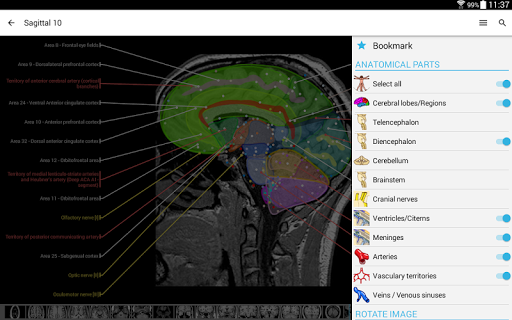

- Seleccione las etiquetas anatómicas por categoría

- Ahora puede ocultar las estructuras una por una (nuevo botón dentro de la ventana emergente de descripción) y visualizarlas nuevamente en el menú derecho